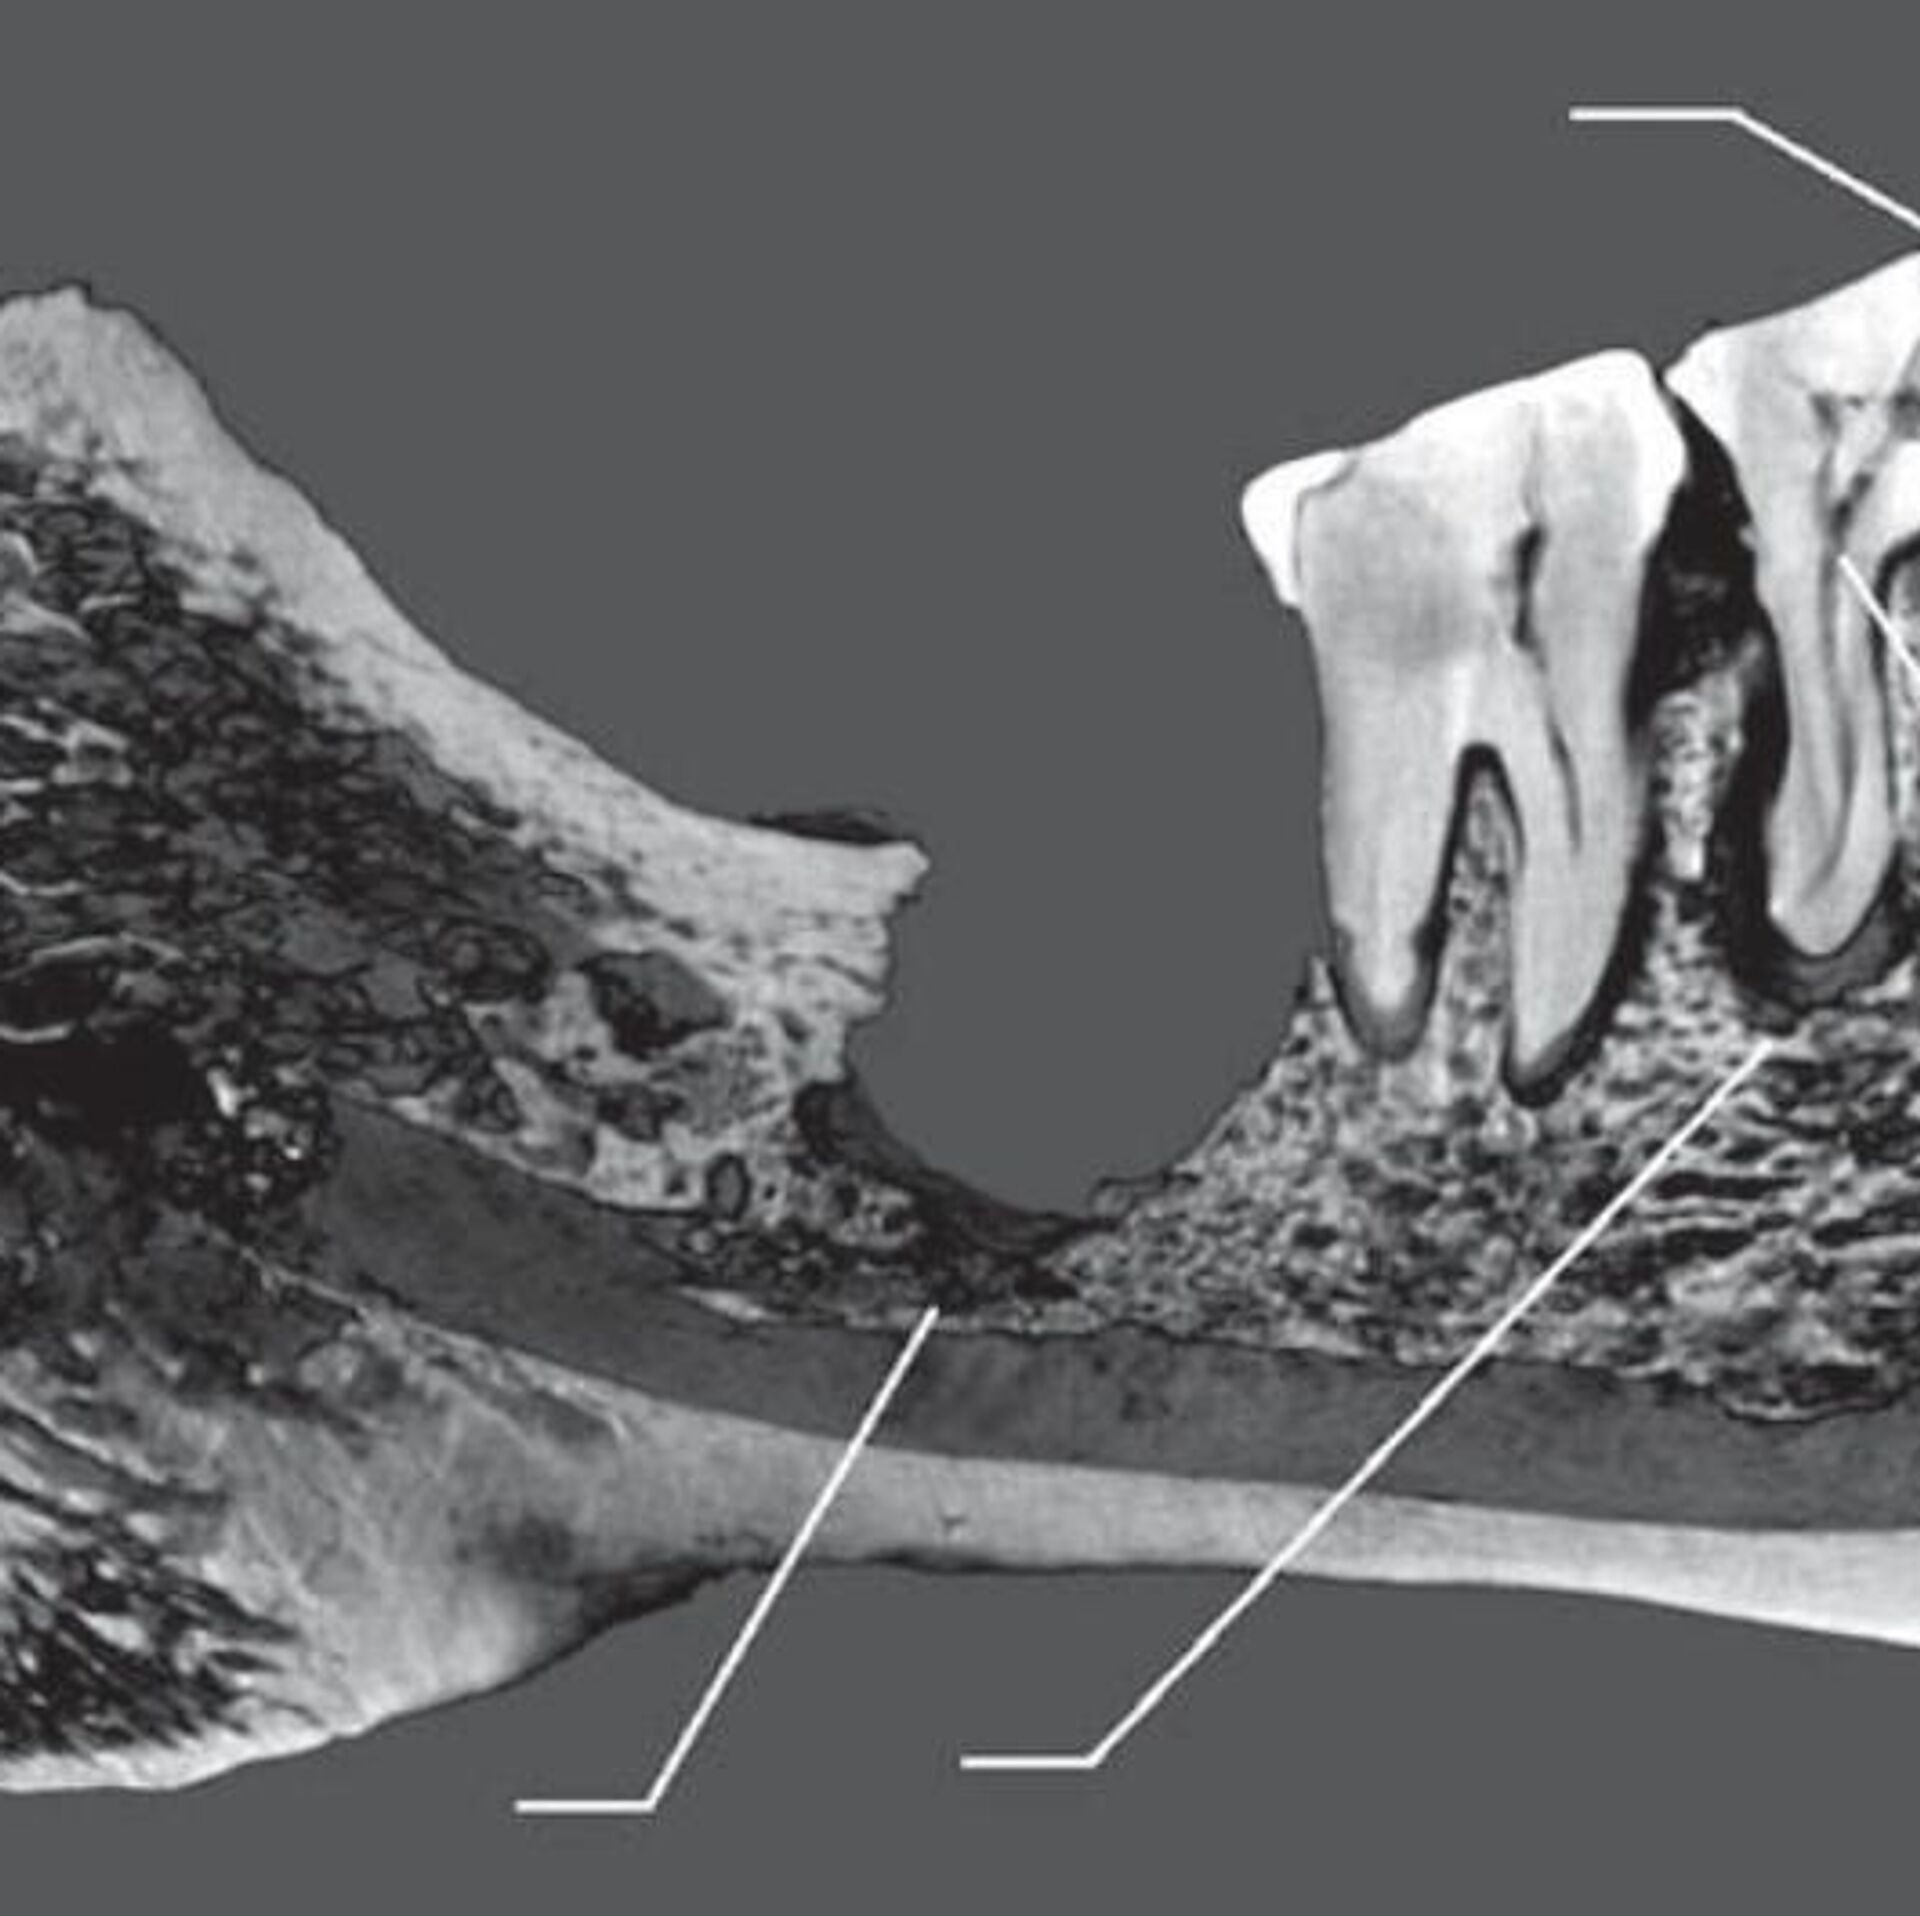

Un grupo explorador del Museo de Antropología y Etnografía de San Petersburgo examinó restos del yacimiento arqueológico Oleneostróvsky, excavado en una isla del norte del lago Onega, en noroeste de Rusia. En una de las tumbas, los científicos encontraron el esqueleto de una mujer adulta de una edad de más de 50 años.

Los paleoantropólogos prestaron atención al cráneo de esta persona porque observaron en él indicios de intervenciones quirúrgicas.

"A la mujer se le cortó el tercer molar junto con un trozo de la mandíbula inferior, y que la operación fue un éxito, por lo que la paciente permaneció con vida al menos varios meses", destaca el artículo publicado en la revista Arqueología, Etnología y Antropología de Eurasia.

En opinión de los autores, esta operación era necesaria porque la caries había provocado el desarrollo de una pulpitis crónica y, posteriormente, de una periodontitis apical y una osteomielitis.

Además, los científicos descubrieron que esta mujer también se fracturó el primer molar del otro lado de la mandíbula cuando, "al parecer, mordió algún objeto duro". Como resultado, el diente se partió en tres trozos, dos de los cuales le fueron extraídos en distintos momentos.

En el alvéolo de este molar, los investigadores registraron una incisión que se hizo para extraer una parte del diente o con otros fines terapéuticos. Sin embargo, la mujer murió poco después de esta operación. De acuerdo con el artículo, probablemente, se desarrolló una inflamación purulenta aguda pocos días después de la intervención, tras la cual la mujer murió de septicemia.

De esta forma, se trata del caso más antiguo conocido de intervención dental hallado en el norte de Eurasia.